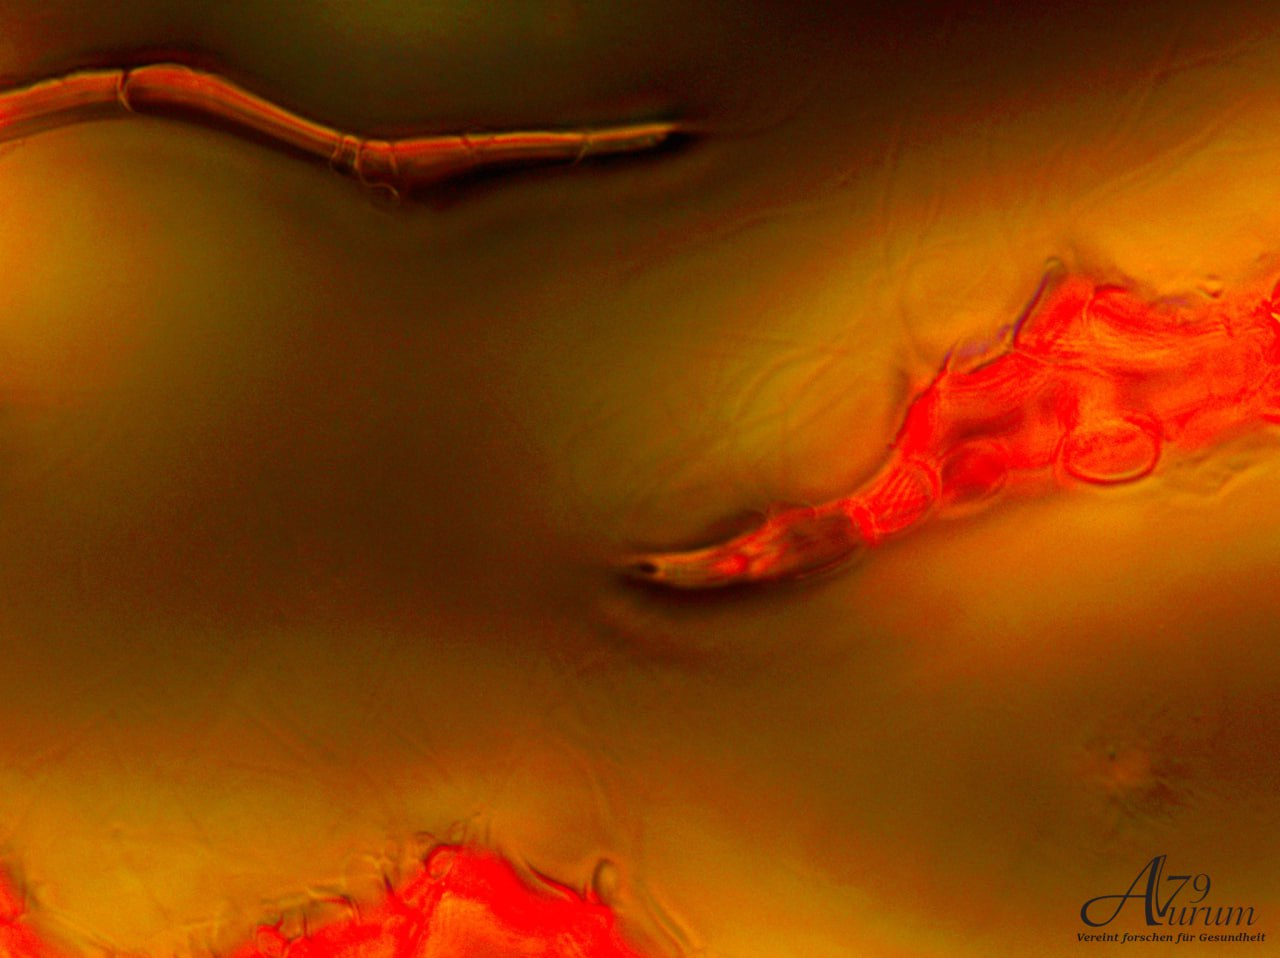

Vitalblutanalyse 4. Tag

Offenbart ein dichtes Netzwerk mit unregelmäßigen, verzweigten Strukturen, möglicherweise Fibrin oder Zelltrümmer. Weniger erkennbare Zellen, könnte auf eine Entzündungsreaktion oder Gewebsschädigung hinweisen. Weitfeld-Okulare mit 10-facher Vergrößerung & 10x Objektiv